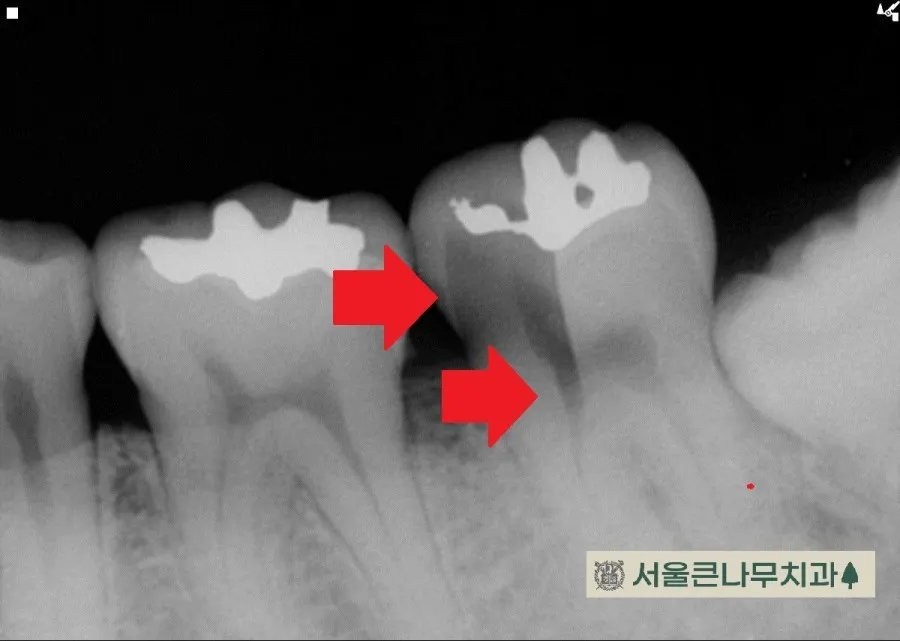

이 사진은 기존에 떼웠던 재료주변으로 변색과 파절이 진행되어 내원하신 분의 경우입니다.

오래된 수복물 주변으로 거무스름한 착색과 크랙이 이어져있습니다. 이렇게 일직선으로 이어진 크랙은 뿌리까지 쪼개져 있을 가능성이 높아 더더욱 위험합니다.

앞에 사진과 마찬가지로 신경치료에 들어간 후 임시치아로 지내게 됩니다.